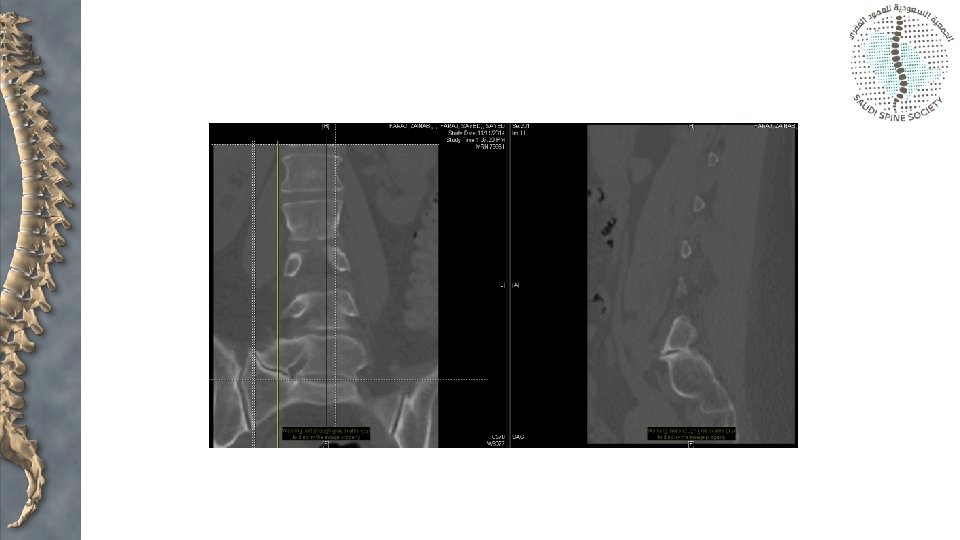

Assessment • X-rays: • • Anteroposterior Lateral Oblique views CT scan

Assessment—Meyerding Classification

Assessment—slip angle Standard method of measurement Method used when inferior end plate of L 5 is irregular

Measurement • Slip angle

Measurement • Slip angle • Normally Negative or 0

Measurement • Sacral inclination • Normally > 30 degrees